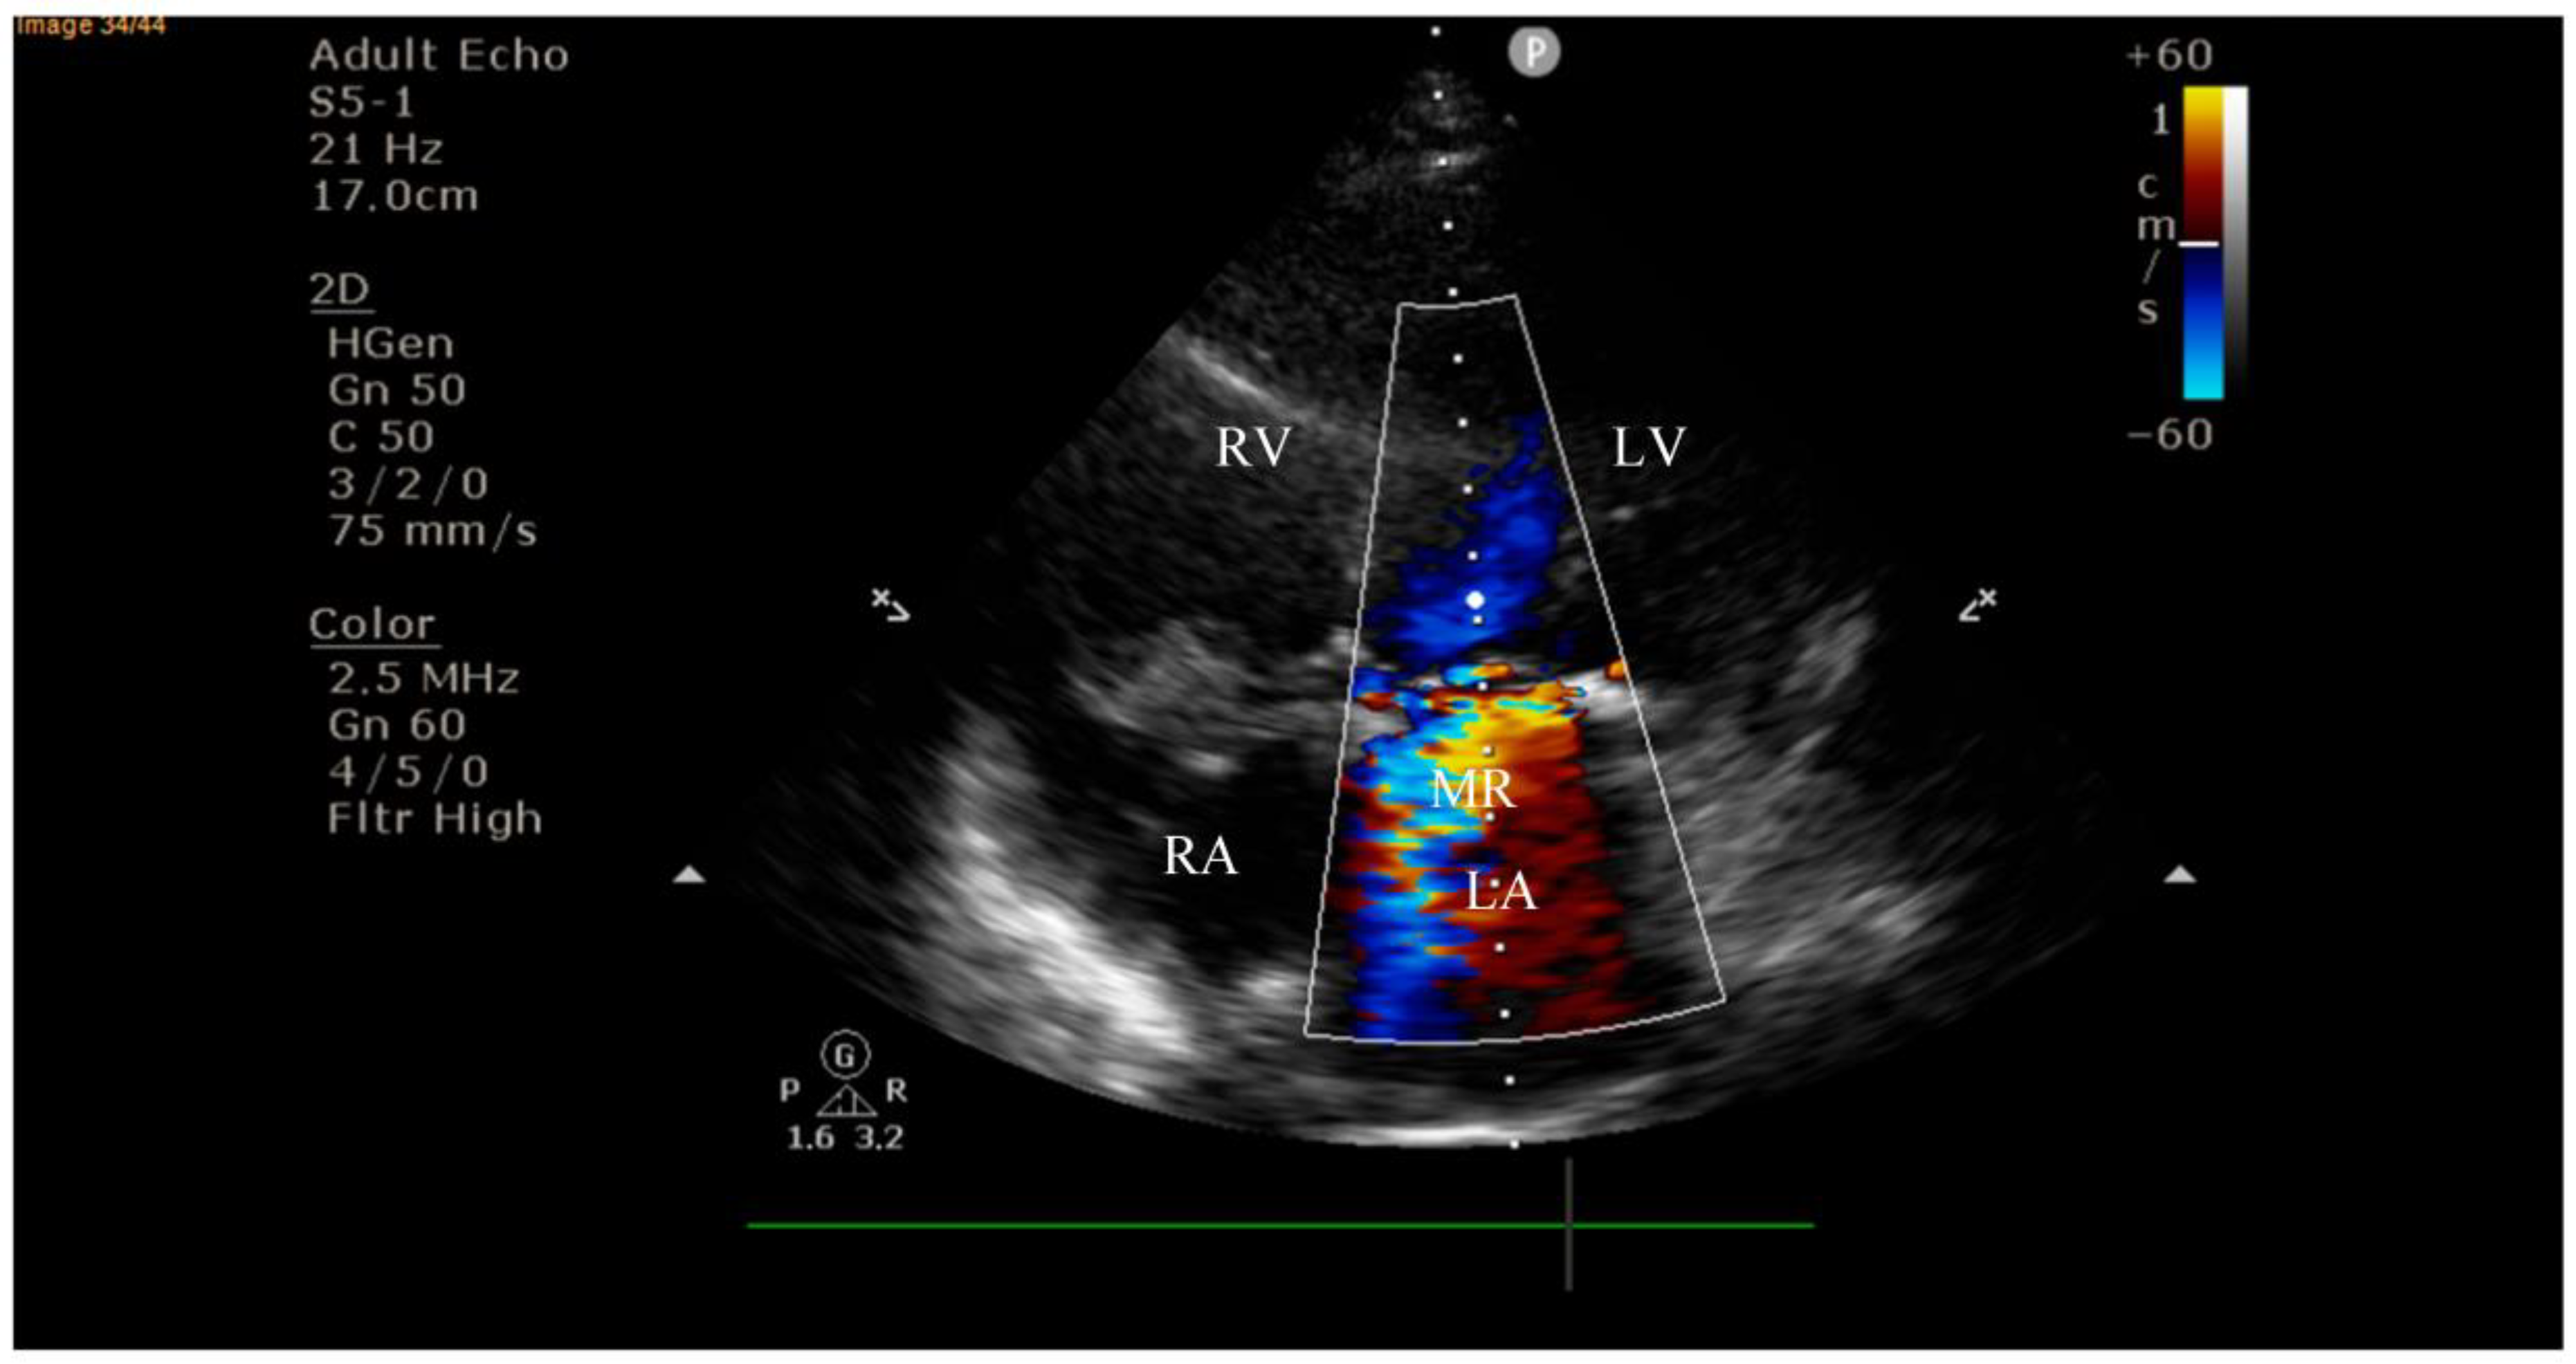

4.2. Diagnostic Findings: Mitral Valve Dysfunction and Embolic Phenomena

4.3. Coronary Complications and Diagnostic Dilemma